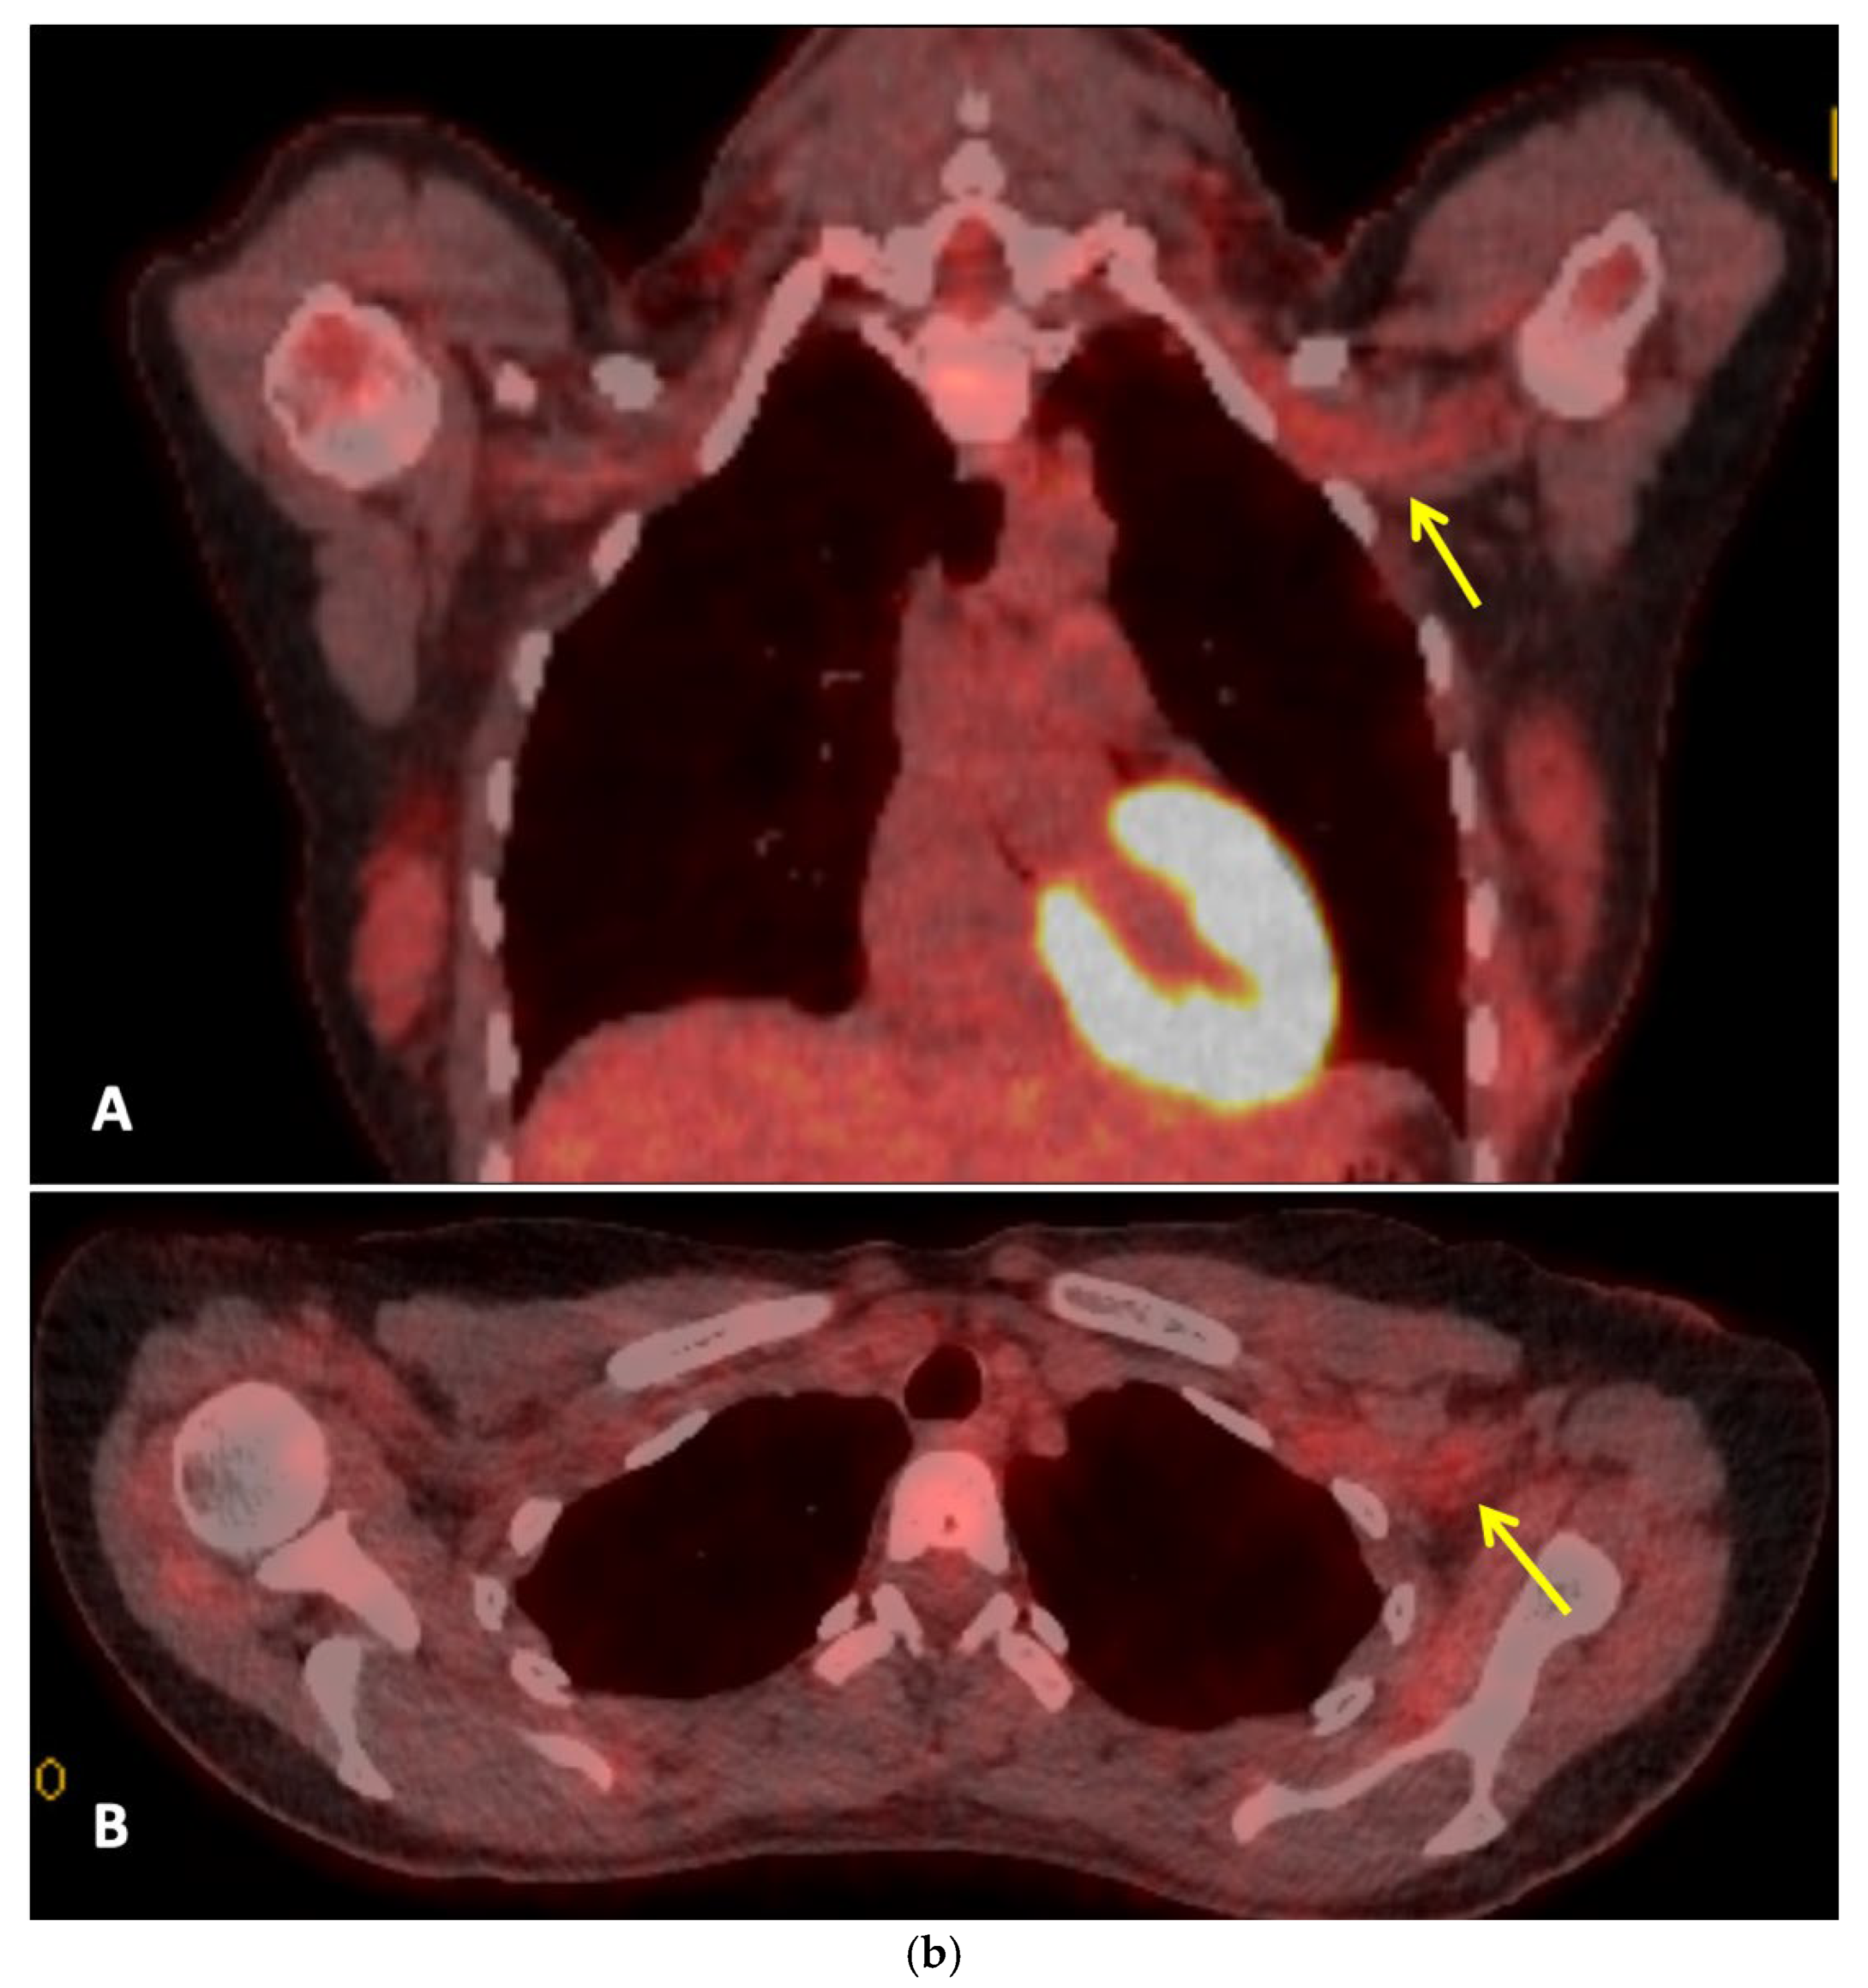

Three months after completing radiotherapy, she developed progressive numbness, paraesthesia, and weakness of the left hand. Examination revealed wasting of the thenar and hypothenar eminences, reduced grip strength, and patchy sensory loss in a C8/T1 distribution. Due to residual cancer burden after surgery, a local recurrence was initially suspected. MRI of the cervical spine and brachial plexus [Figure 2a] did not demonstrate metastatic disease, but findings were consistent with brachial plexitis. No recurrent disease was identified on PET-CT but asymmetric low grade uptake in the left brachial plexus was also consistent with brachial plexitis [Figure 2b] confirmed absence of malignancy. Electromyography (EMG) [Figure 3] and nerve conduction studies demonstrated denervation consistent with a lower-trunk brachial plexopathy; onconeuronal antibody serologies were negative.

Figure 2. a: MRI Brachial Plexus: This is a figure. Images A and B are coronal and axial T2 STIR images which demonstrate thickening and increased T2 signal of the brachial plexus on the left (yellow arrows). Normal size and signal of the brachial plexus on the right for comparison (white arrow). Images C and D are coronal and axial T1 fat saturated post contrast images which demonstrate abnormal hyperenhancement of the thickened brachial plexus on the left side (yellow arrows). Findings are consistent with left brachial plexitis. b. Whole Body FDG PET-CT: This is a figure. Images A and B are coronal and axial fused PET-CT images of the thorax. They demonstrate asymmetric low grade uptake in the left brachial plexus (yellow arrows) compared to the right side but there is no soft tissue mass or high grade uptake to suggest metastatic disease.